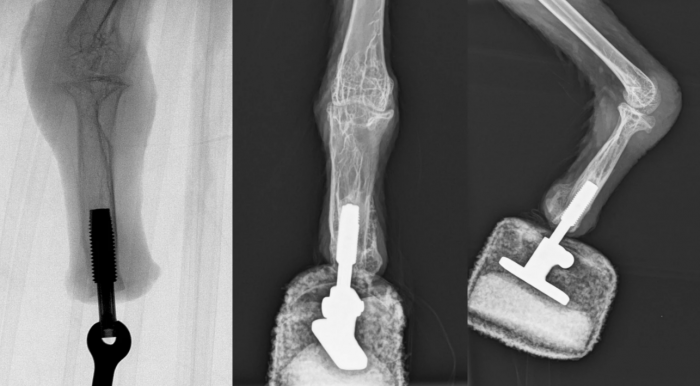

对于这只胡兀鹫,该小组利用了一种被称为骨整合的过程,在这个过程中,人造假肢的底部直接与鸟类残余残肢的腿骨末端连接。“米娅”在手术后三周内开始尝试行走,并在六周后将它的全部重量放在脚上。据报道,它现在可以正常行走和着陆。

Aszmann说:“这个概念提供了一个高度的体现,因为骨感知提供了直接的直观反馈,从而允许自然地使用肢体进行行走和捕食。我们现在第一次成功地以仿生方式重建了一只秃鹰的肢体。”